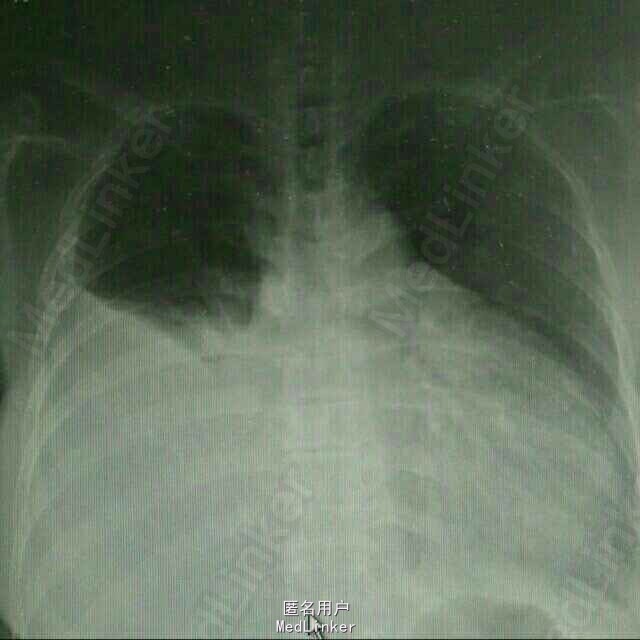

患者,女性,52岁。 2015年3月 因右侧胸腔积液,至外院就诊,胸水中找到腺癌细胞,胸部CT见右下肺占位。后多次胸腔闭式引流,但效果差。期间胸水脱落细胞检测EGFR,有突变,故口服靶向药物,并国产培美化疗一次。最近又出现心包积液,致呼吸困难入院。

入院后予以胸水引流,复查ct,行心包穿刺引流,改善症状,加强营养,纠正低蛋白。情况稳定后,在全麻下行右侧胸腔持续热灌注化疗,术中胸腔镜见胸壁大量转移病灶,取部分组织送检EGFR。术后经密切观察治疗,度过热疗损伤急性期。症情平稳后出院。术后EGFR阴性。

术后一月复查胸部CT,右肺较前进一步好转,并行力比泰+顺铂化疗。目前继续后续治疗,计划力比泰长期维持。